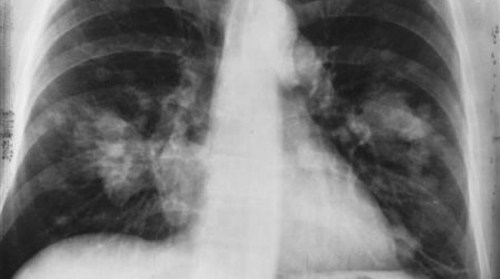

تقرير: سرطان الرئة.. 10 علامات رئيسية يجب ألا يتم تجاهلها يعتبر سرطان الرئة أحد أكثر أنواع السرطانات شيوعاً في العالم، حيث بلغ عدد المصابين به حول العالم العا...